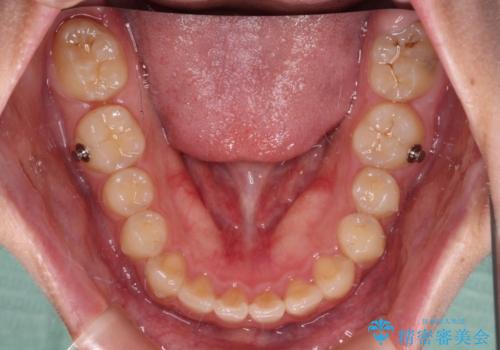

- 深い咬み合わせと上顎前歯の突出感を気にして来院された患者様です。

当院では通常、臼歯の咬合が理想的な位置に対して上顎が前方位にある場合。ワイヤー矯正または補助装置の併用したインビザライン矯正を選択しています。

今回は、できるところまででいいのでインビザライン単体で治療をしたいという希望があったため、インビザラインにて矯正治療を行うこととしました。

正面や横からの写真ではきれいに治っており、患者様は大変満足のいく仕上がりとなりましたが、深い咬み合わせの改善は不十分で、奥歯の咬み合わせも改善させることができませんでした。

インビザラインは、咬合力の強い方ですと、奥歯が歯肉内にめり込んでしまうため、前歯が強く接触してしまうことがあります。

こちらの方は、奥歯はしっかりと噛んだのですが、歯肉にめり込んでしまったことで、歯肉が腫れやすくなってしまいました。